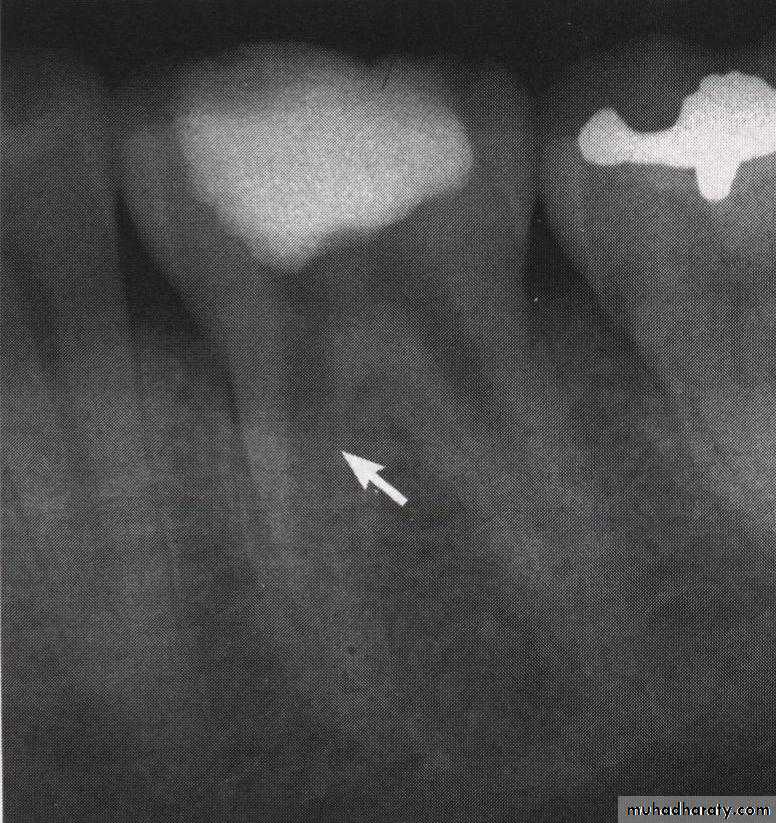

Repair of stripping perforation (arrow)